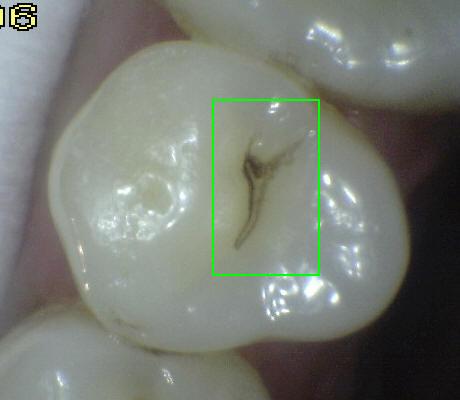

Código 3:

Ruptura localizada del esmalte debido a caries sin dentina visible

- El diente visto en estado

húmedo pueden tener una clara opacidad de caries (lesión de

mancha blanca)

y / o decoloración marrón de caries que es más ancha que la

fisura natural y la fosa, que no es consistente con la

apariencia clínica de esmalte sano. Una vez seco, se

observa una pérdida de estructura dental cariada en la

entrada, o dentro de la fosa o fisura . Esto se ve

visualmente como evidencia de desmineralización en la

entrada o dentro de la fisura o fosa, y aunque la fosa o

fisura puede aparecer sustancialmente más ancha que lo

natural, la dentina no es visible en las paredes o la base

de la cavidad ó discontinuidad .

En caso de duda, o

para confirmar la evaluación visual, la sonda de la OMS /

IPC / PSR puede ser

utilizada con cuidado a través de la superficie del diente,

para confirmar la presencia de una cavidad ( < 0,5mm.de

profundidad) al parecer limitada al esmalte . La

identificación de la cavidad se consigue deslizando el

extremo de la bola a lo largo de la fosa o fisura

sospechosa.